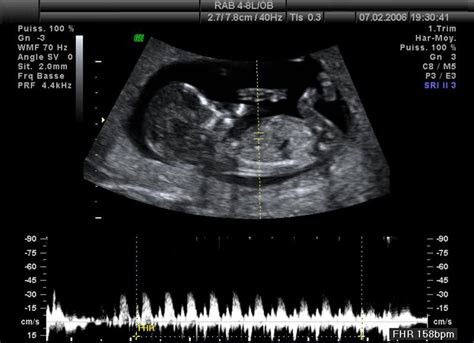

Dozviem sa pohlavie bábätka?Hoci mnohé mamičky považujú určenie pohlavia za hlavný cieľ tohto ultrazvuku, je dôležité zdôrazniť, že jeho primárnou úlohou sú morfologické merania a diagnostika. Ultrazvuk v 20. týždni je predovšetkým detekčným a diagnostickým nástrojom, ktorý umožňuje lekárovi sledovať vývoj a zdravie plodu. Počas vyšetrenia sa zvyčajne kontroluje veľkosť hlavičky, bruška, končatín, pozoruje sa poloha, pohyb a srdcová frekvencia plodu. Sleduje sa aj stav placenty a množstvo plodovej vody. Samozrejme, často sa pri týchto kontrolách ukáže aj pohlavie dieťaťa, ale nie je to pravidlo a nie je to jeho hlavný účel.

Prvé veľké ultrazvukové vyšetrenie, známe aj ako druhý screening alebo morfologický ultrazvuk, sa u nás zvyčajne vykonáva medzi 18. a 22. týždňom tehotenstva. Jeho hlavným cieľom je komplexné posúdenie vývoja plodu. Lekár zisťuje počet plodov, presne meria jednotlivé časti tela plodu, vypočítava jeho vek a hmotnosť a hľadá prípadné vrodené vývojové chyby. Sleduje sa tiež činnosť srdca, množstvo plodovej vody a uloženie placenty. Zmyslom tohto vyšetrenia je teda zistiť, či sa vaše dieťatko vyvíja normálne a či sú jeho orgány správne sformované.

Samotné skenovanie trvá približne 15 až 20 minút a je úplne bezbolestné. Lekár na bruško nanesie špeciálny gél, ktorý slúži ako vodič zvukových vĺn. Následne pohybuje snímačom po bruchu v rôznych smeroch. Počas vyšetrenia lekár hľadá akékoľvek abnormality, skúma fyzický rast a vývoj dieťaťa a kontroluje polohu placenty. Na obrazovke uvidíte svoje dieťa, čo je pre rodičov mimoriadne vzrušujúci zážitok. Je dôležité vedieť, že prípadné odchýlky, ktoré lekár zaznamená, ešte nemusia znamenať vážny problém s dieťatkom, ale slúžia na ďalšie sledovanie a prípadné špecializované vyšetrenia.

V 20. týždni tehotenstva (skrátene 20. tt) vaše bábätko dosahuje dĺžku približne 16,4 cm od hlavy po zadoček a od hlavy po päty meria okolo 25 cm. Jeho váha sa pohybuje okolo 300 až 350 gramov. V tomto období sa rýchlo vyvíja časť mozgu zodpovedná za zmysly. Tep srdca je silnejší a ľahko zistiteľný pomocou Dopplerovho prístroja.